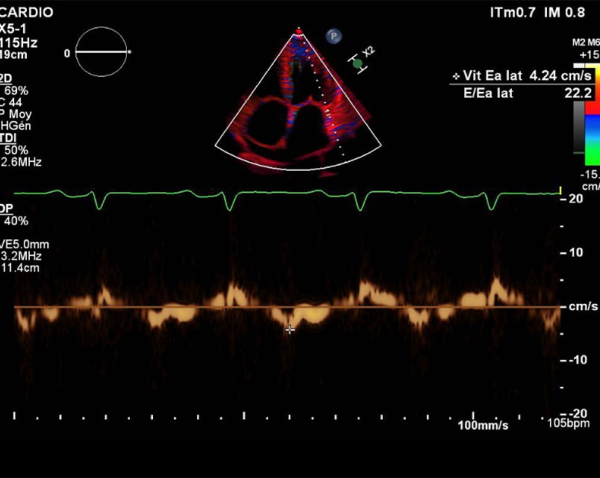

- Profil mitral restrictif, pressions de remplissage VG élevées (E/A =2.6, E/e’ moy = 22)

- Fonction VD altérée (TAPSE = 7.7mm, S tric = 5.9cm/s)